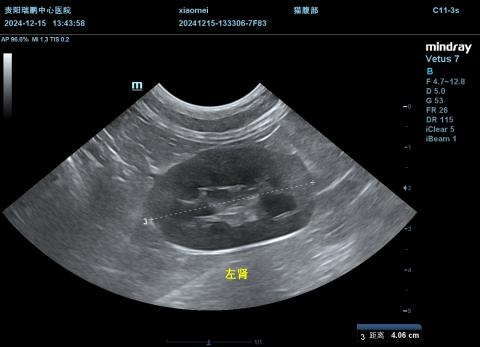

2.4.2腹部超声(12.15)

打开网易新闻 查看精彩图片

图23-34

结果提示:

①肝脏肿大,肝静脉轻度扩张,怀疑充肝被动充血、肝炎,建议结合临床及其他检查诊断;

②胃扩张积液,蠕动迟缓,疑似胃炎;

③少量腹腔积液。